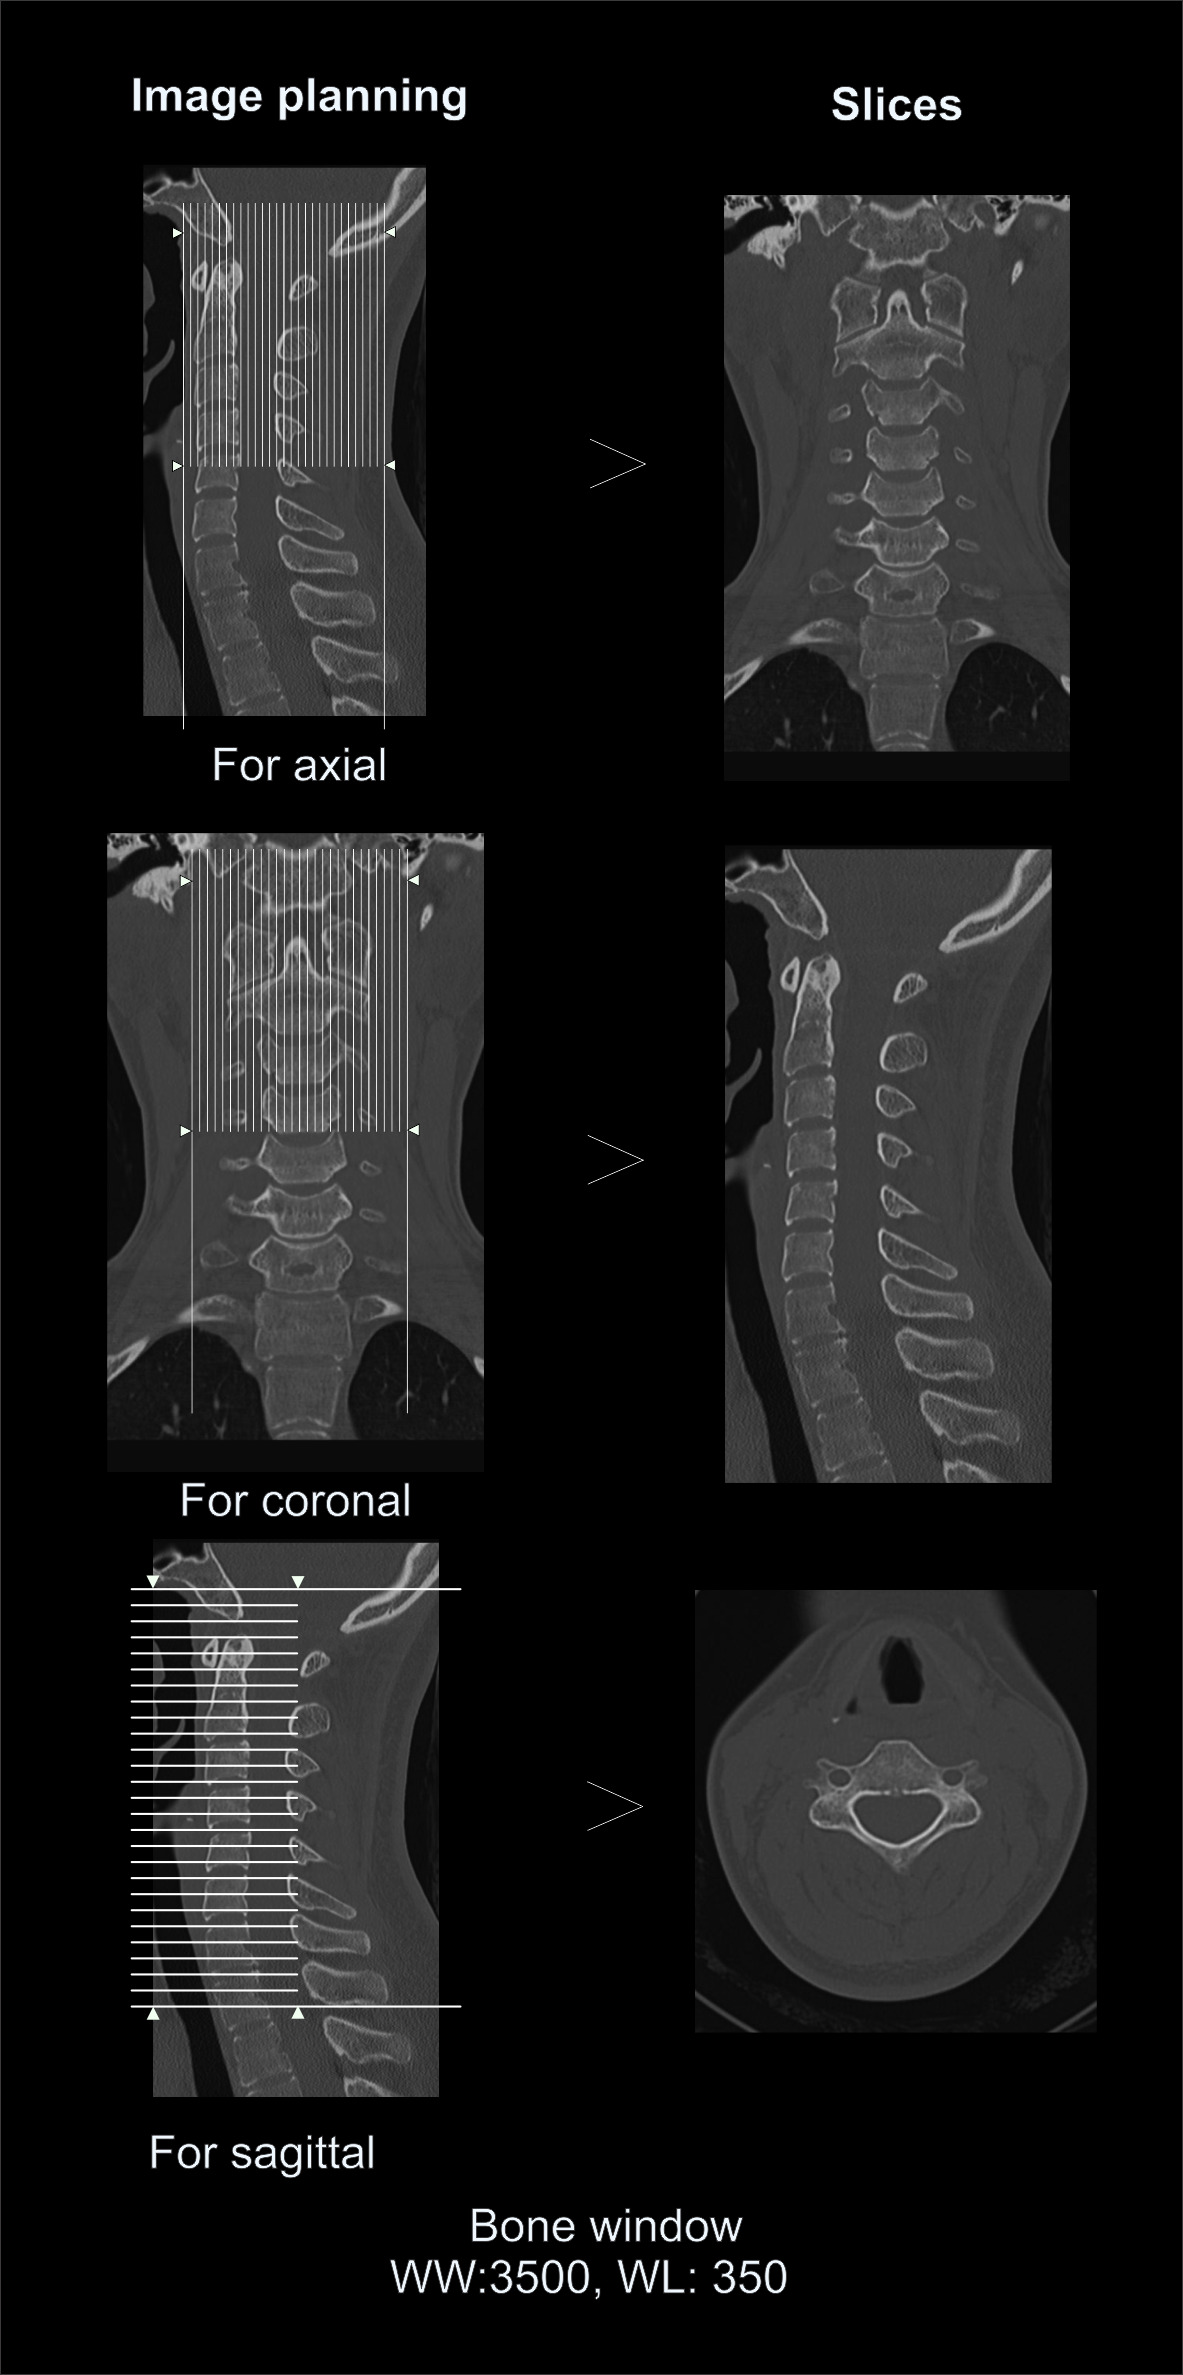

Post-processing

- Sagittal and coronal images with ≤ 2 mm slice thickness in bone window (WW: 3500, WL: 350).

- Contagious axial slices in bone window and soft-tissue window (WW:500, WL:50) with ≤ 2mm and ≤ 3mm slice thicknesses respectively.

- Oblique reformats perpendicular to the long axis of the neural foramina on both sides.

Explanation: for the evaluation of neural foraminal stenosis.

- Additionally, 3d images to show Cervical-spine.